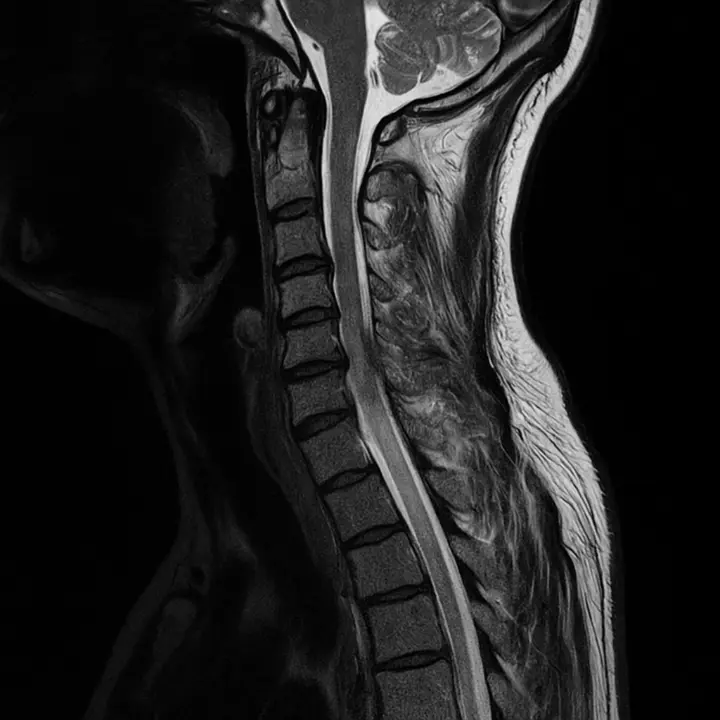

- Resonancia magnética (RM): La RM es la prueba más precisa para evaluar los discos intervertebrales, ya que permite ver con detalle la degeneración de los discos y la presencia de hernias discales o compresión de los nervios.